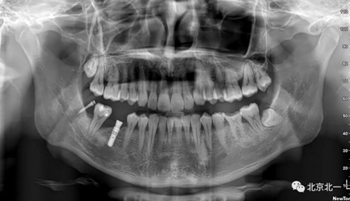

CBCT:骨量高度及寬度可, 48埋伏,低位阻生.37近中骨吸收

診斷:下頜牙列缺損, 48低位埋伏阻生 37 牙周炎

術(shù)后拍片。